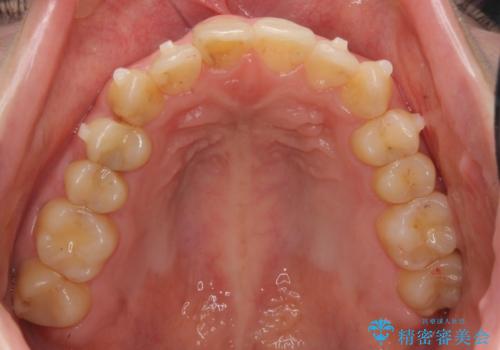

犬歯のねじれ 上の歯が引っ込んでいる

- 前歯の並びを気にして来院。

インビザラインで、上の前歯をやすり掛けして並べました。

途中妊娠、出産を挟み、患者様がアライナーがつけられない時期もあって治療自体は延長しました。